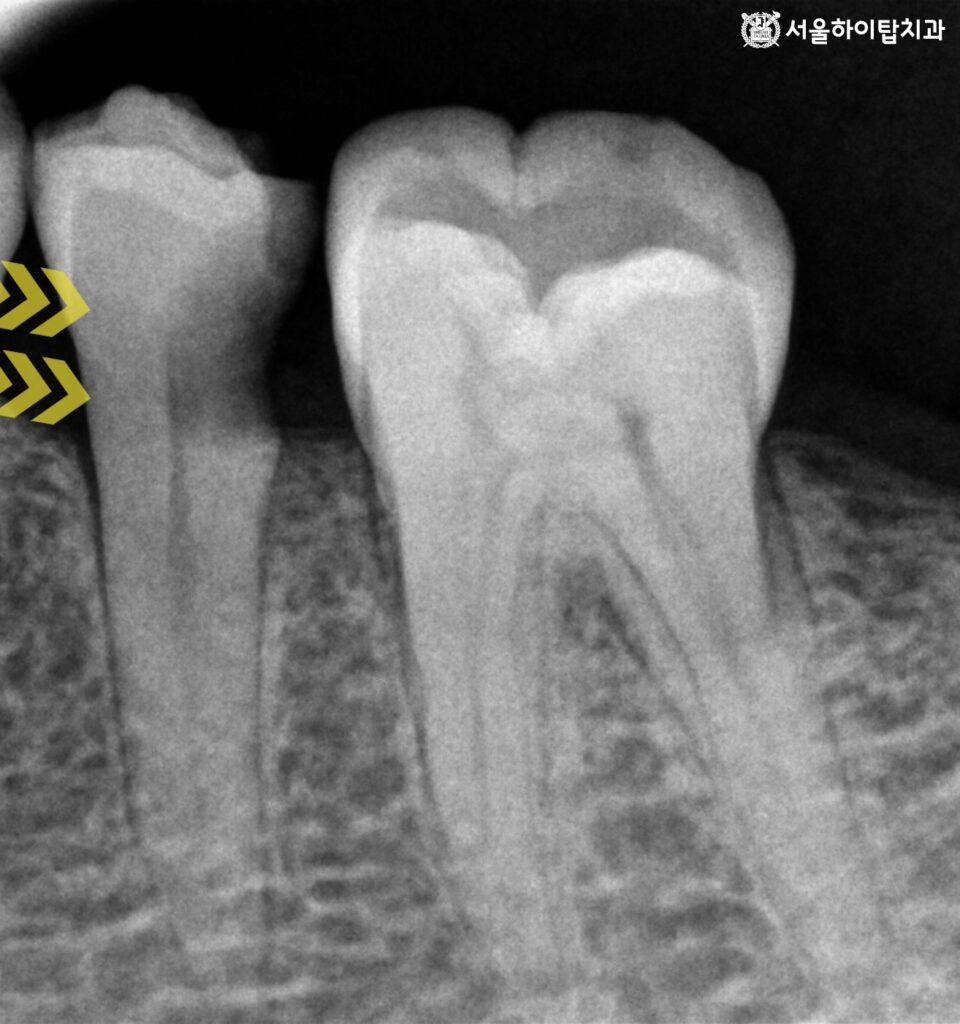

처음 내원 당시 촬영된 파노라마 엑스레이를 보면

해당 병변은 치아 인접면 부위에서 시작된 초기에서 중기 단계의 우식으로 보입니다.

이 단계에서는 아직 치수까지 직접적인 침범이 이루어지지 않은 상태로,

적절한 시기에 치료가 진행된다면 신경치료 없이

보존적 처치를 통해 충분히 치아를 유지할 수 있습니다.

해상도가 높은 PA(Periapical) 사진상에서는

우식이 치수와 비교적 근접해 있는 양상이 관찰되지만,

간석오거리역 치과 에서는 명확한 치근단 병소나

치수 괴사를 시사하는 소견은 보이지 않습니다.

따라서 당시에는 보존 치료를

우선적으로 고려할 수 있는 상황이었습니다.